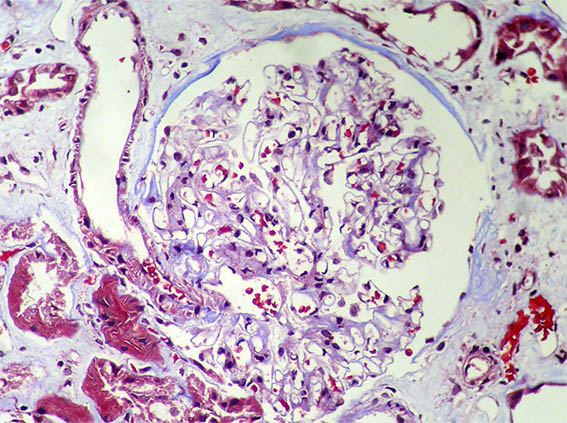

Kidney biopsy is done. Look at the pictures.

Figure 6. Masson's trichrome stain, X200.